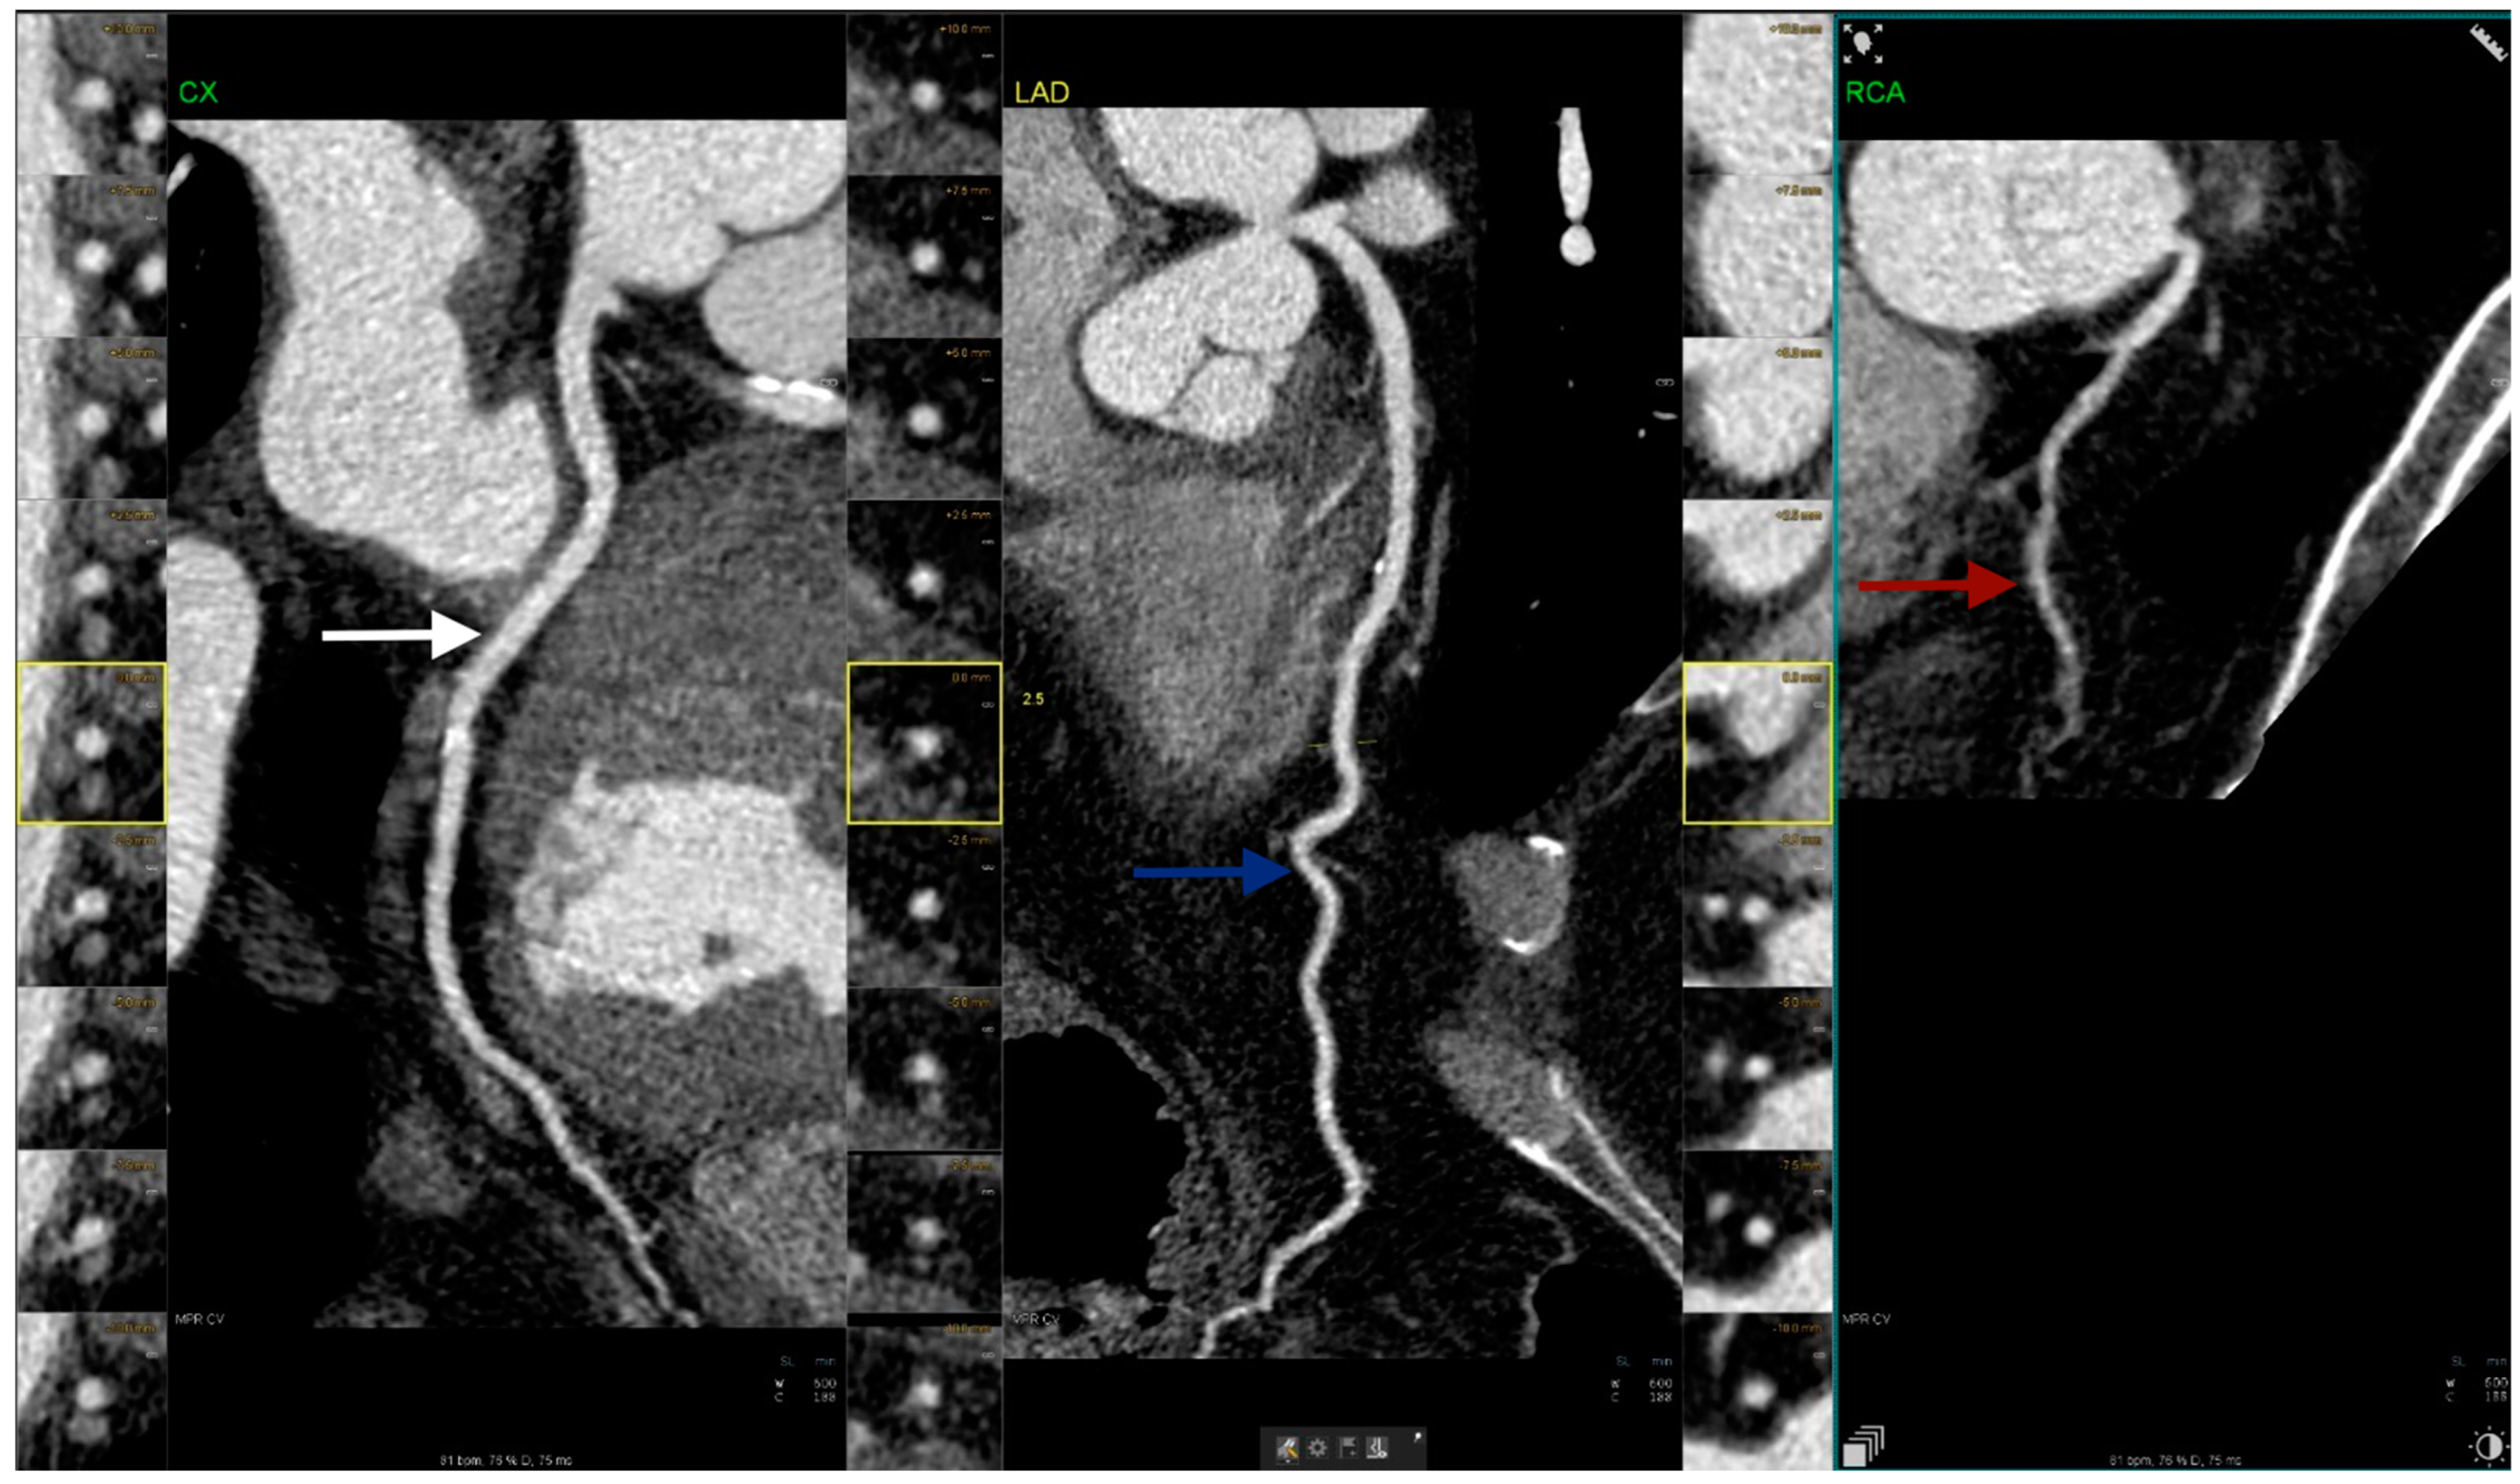

| Coronary artery hypoplasia | 71 | 20.3% | 0.5% |

| Patients (n) | Gender | Hypoplastic Coronary Artery | Stenotic Coronary Artery with Stent Placement |

|---|---|---|---|

| 1 | M | LM | LAD |

| 2 | M | RCA | LAD |

| 3 | F | LAD | LAD |

| 4 | M | LM | LAD |

| 5 | M | RCA | LCx |

| 6 | M | LM | LCx |

| 7 | M | LAD | RCA |